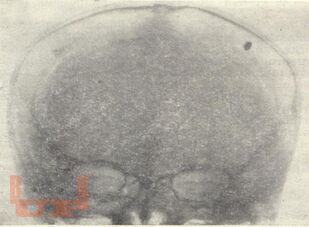

В методических рекомендациях представлены классификация огнестрельных ранений черепа по Н.С. Косинской, включающей непроникающие и проникающие ранения черепа, рентгенодиагностика таких ранений. Подробно описаны особенности краниографии, определение внутричерепного или внечерепного положения инородных тел. Как правило, при краниографии снимается сторона поражения, что не годится для определения инородных тел в височных отделах. Авторы рекомендуют в таких случаях возродить мало известное предложение Г.Н.Трейстера и Р.Н.Смелянского – рентгенографировать череп на здоровой стороне касательным рентгеновским лучом. Значительное место уделено топической характеристике инородных тел в черепе и мозговом веществе, воспроизведению раневого канала на снимках по И.С. Бабчину.

Методические рекомендации иллюстрированы снимками военного времени, схемами, дан краткий список литературы. Методические рекомендации предназначены для интернов, ординаторов, рентгенологов.